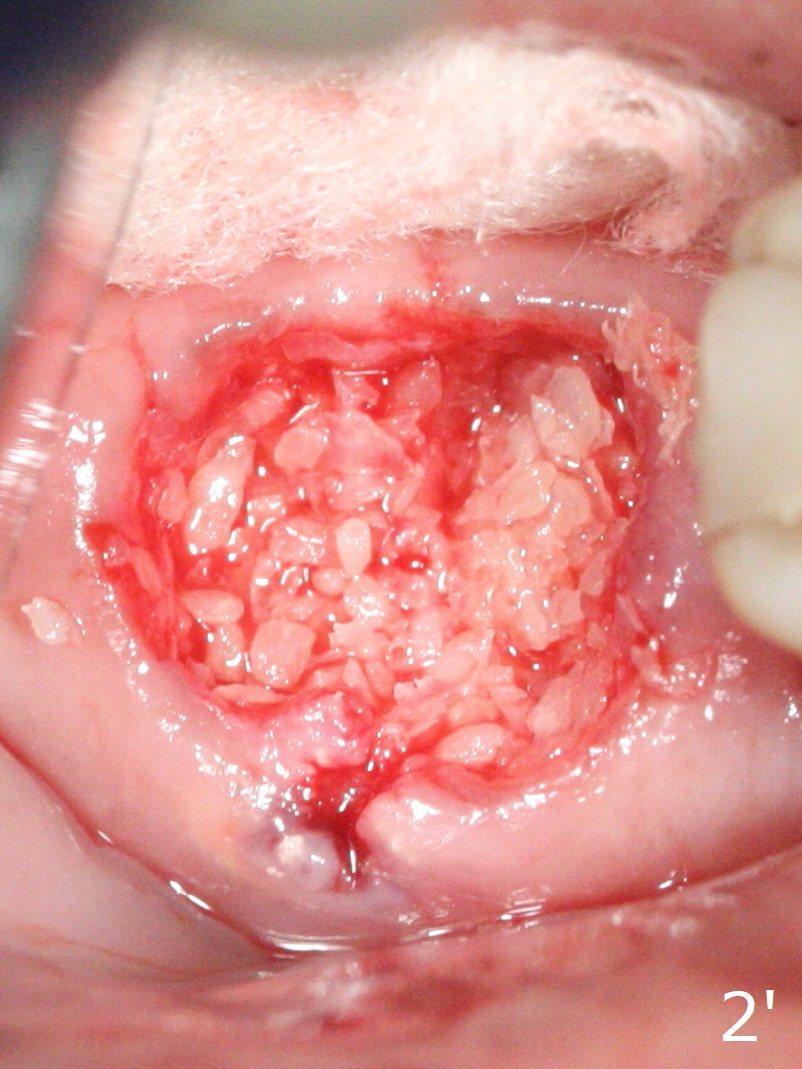

Amazingly bone graft granules seem to stick to each other (semi sticky bone (Fig.2), as compared to PRF).

Semi Sticky Bone     Last     Next     Lower Magnification